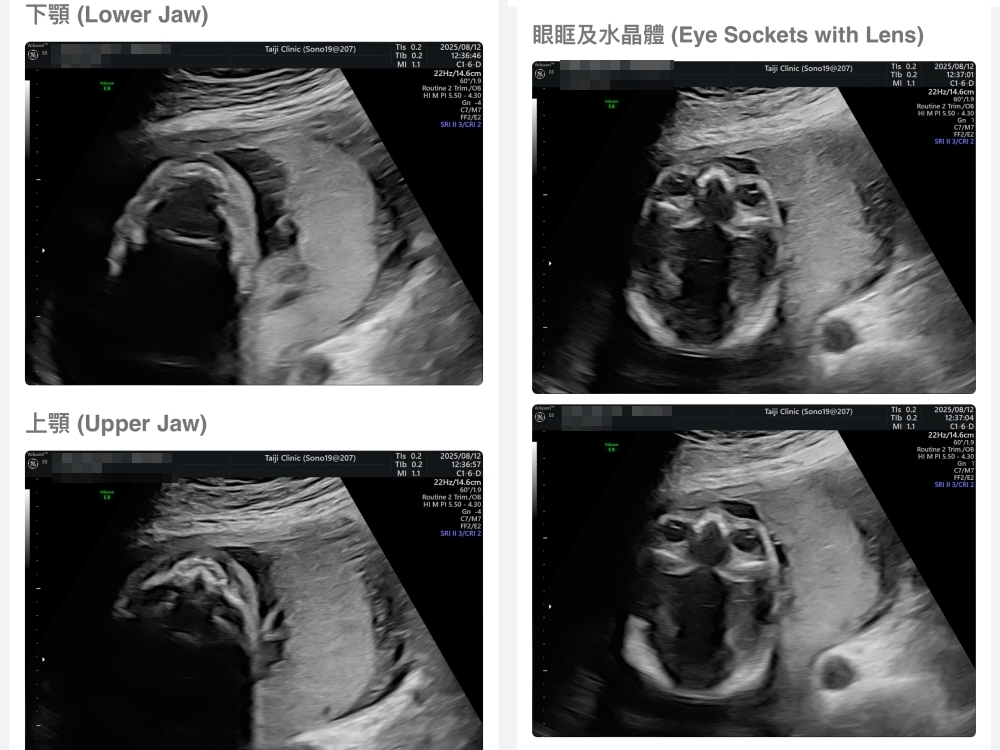

▲離開診所後會收到MAIL,我們14:05離開,大約是16:45收到mail,裡面會有滿滿的超音波照片,紀錄的很詳細!也會提供紙本的報告,可以給日後產檢的醫師做參考👌